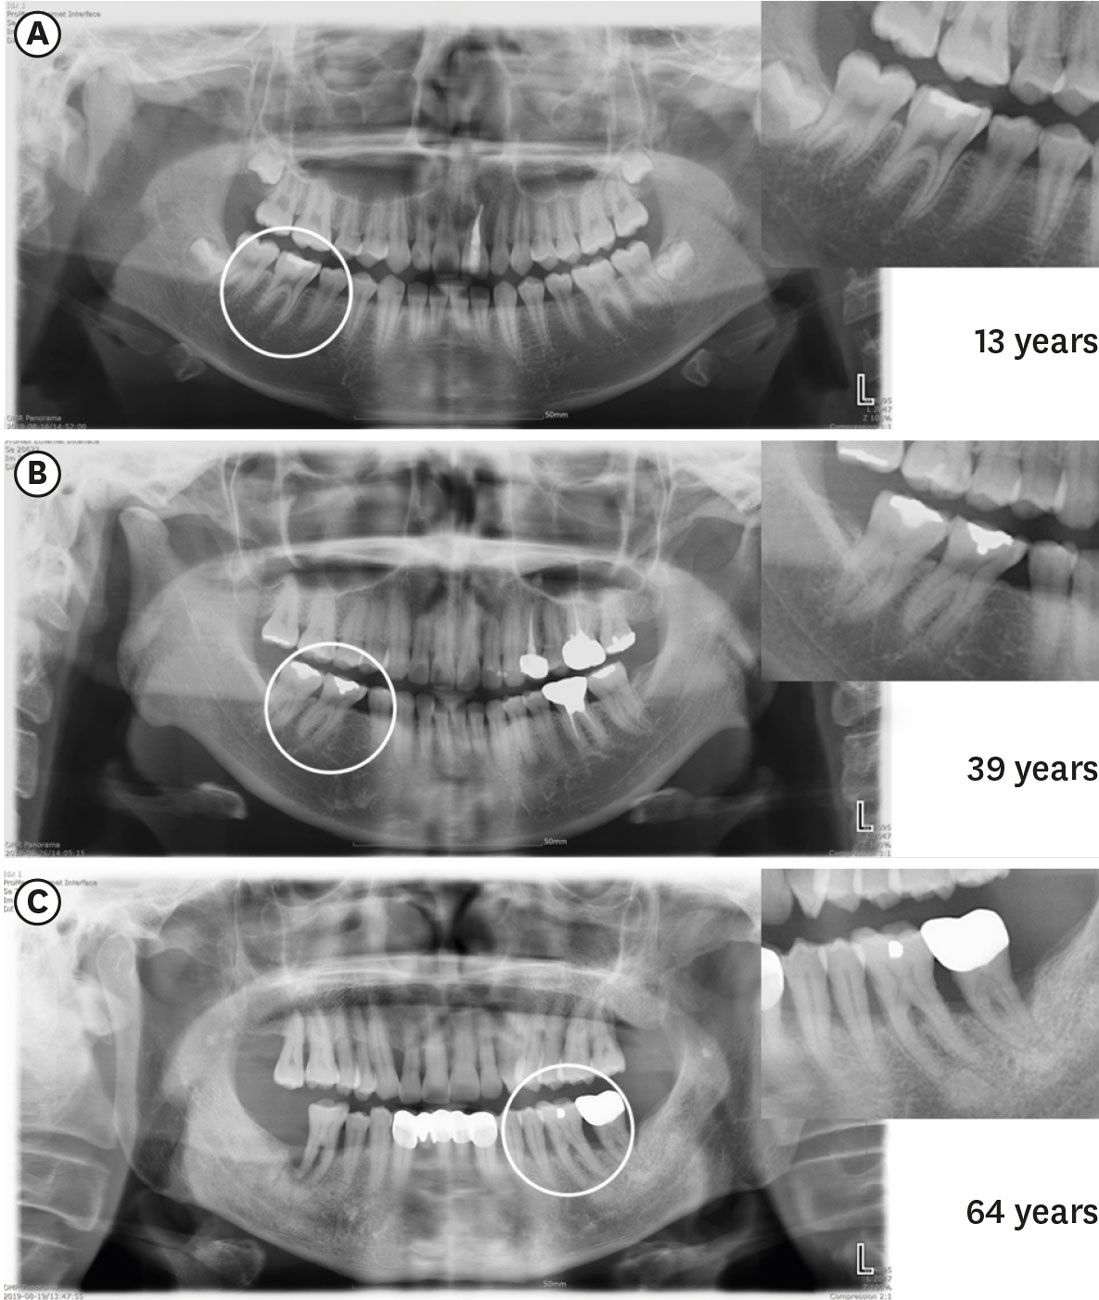

The incidence of canal isthmuses appears to be age-related [28]. Individuals who are 20 years old or less have wide and oval canals without isthmuses at the early stages of root development [29]. In individuals between 20 and 40 years old, the deposition of secondary dentin in the mesiodistal direction results in the formation of 2 canals with an isthmus [29,30]. Up to 81% of mesial roots of the mandibular first molars of individuals aged 20-39 years old have isthmuses, particularly at apical 4 to 6 mm [29]. In individuals who are 40 years old or more, the prevalence and volume of isthmuses significantly decrease, and the canal becomes completely separated. In individuals who are over 50, the prevalence of isthmuses was found to be 16.7% [31] and only 24% of individuals over 60 years of age had isthmuses in mesial roots of the mandibular molars [29]. The ratio of partial isthmuses to complete isthmuses has been shown to increase with age [29,32]. Figure 2 shows the characteristics of isthmuses at different ages with axial cone-beam computed tomography images.

Figure 2. Axial cone-beam computed tomography images of 3 mandibular first molars, showing isthmuscharacteristics at different ages. (A) Individuals under 20 years old (18 years): a wide canal without an isthmus, (B)individuals between 20 and 40 years old (38 years): an isthmus in the mesial root, (C) individuals who are 40 years old or more (62 years): sclerotic mesial canals without an isthmus, resembling a single canal.